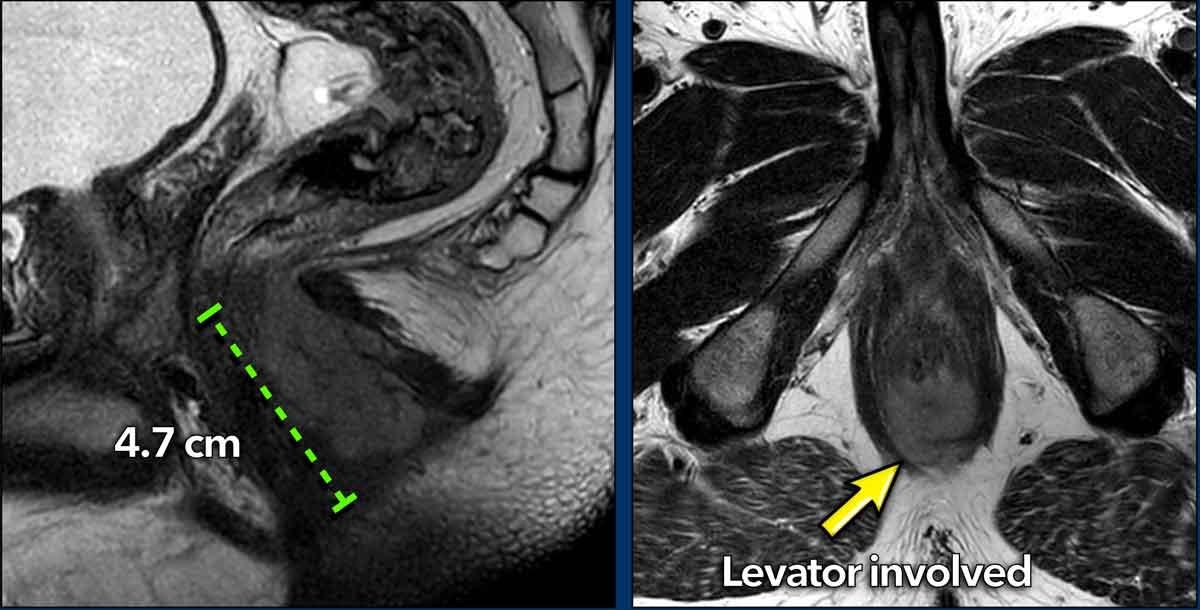

Định nghĩa bệnh T4 khác nhau giữa ung thư hậu môn và ung thư trực tràng.

Khác với ung thư trực tràng, xâm lấn cơ thắt ngoài (*) và các cơ sàn chậu (*) không được xếp vào giai đoạn T4 khi phân giai đoạn ung thư hậu môn.

Ví dụ này cho thấy một khối u có đường kính tối đa 4,7 cm.

Trên mặt cắt ngang, khối u xâm lấn cơ thắt trong từ vị trí 4 giờ đến 8 giờ.

Khối u lan vào khoang gian cơ thắt và xâm lấn cơ nâng hậu môn ở phía lưng bên phải (mũi tên).

Trong trường hợp ung thư hậu môn, tổn thương này được phân giai đoạn T2 (đường kính 2-5 cm), trong khi nếu là ung thư trực tràng, sự xâm lấn cơ thắt ngoài và cơ nâng hậu môn sẽ cấu thành giai đoạn T4.